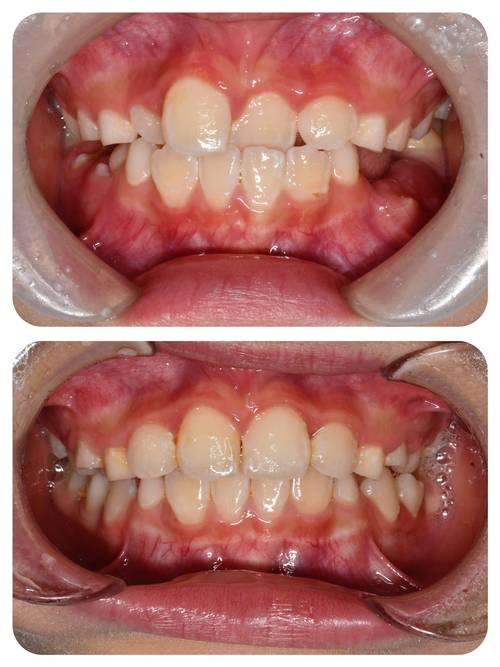

牙齿排列不齐、咬合异常等问题在儿童中较为常见,如“地包天”“龅牙”“牙齿拥挤”等,这些问题若不及时干预,可能导致一系列危害:一是影响咀嚼功能,降低食物消化吸收效率;二是增加龋齿、牙周病风险,因为错位牙难以清洁;三是可能影响发音,如“地包天”可能导致发音不清;四是对面部美观造成影响,导致孩子产生自卑心理,甚至影响社交发育,部分错颌畸形(如上颌前突、下颌后缩)还可能伴随颌骨发育异常,早期干预可引导颌骨正常生长,避免成年后需要正颌手术的复杂治疗。

- 恒牙早期(11-14岁):此时大部分恒牙已萌出,颌骨发育接近成熟,是进行固定矫正的“黄金时期”,主要解决牙齿拥挤、牙列稀疏、深覆合、深覆盖等问题,通过传统托槽矫正或隐形矫正排齐牙齿,调整咬合关系。